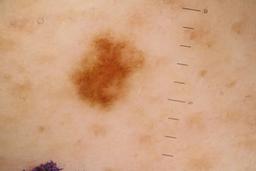

ISIC_5852089

Public

Information

- Created

- Dimensions

- 5184 x 3456

- Attribute to

- Sydney Melanoma Diagnostic Center at Royal Prince Alfred Hospital, Pascale Guitera

- License

- CC-BY-NC

- Used in

- Challenge 2020: Training

- Belongs to

- IP_9124285 IL_2074851

Clinical

| Field | Value |

|---|---|

| acquisition_day | 1173 |

| age_approx | 55 |

| anatom_site_1 | Lower extremity |

| anatom_site_2 | Foot |

| anatom_site_special | acral NOS |

| concomitant_biopsy | False |

| diagnosis_1 | Benign |

| diagnosis_confirm_type | serial imaging showing no change |

| fitzpatrick_skin_type | II |

| image_type | dermoscopic |

| lesion_id | IL_2074851 |

| patient_id | IP_9124285 |

| sex | male |